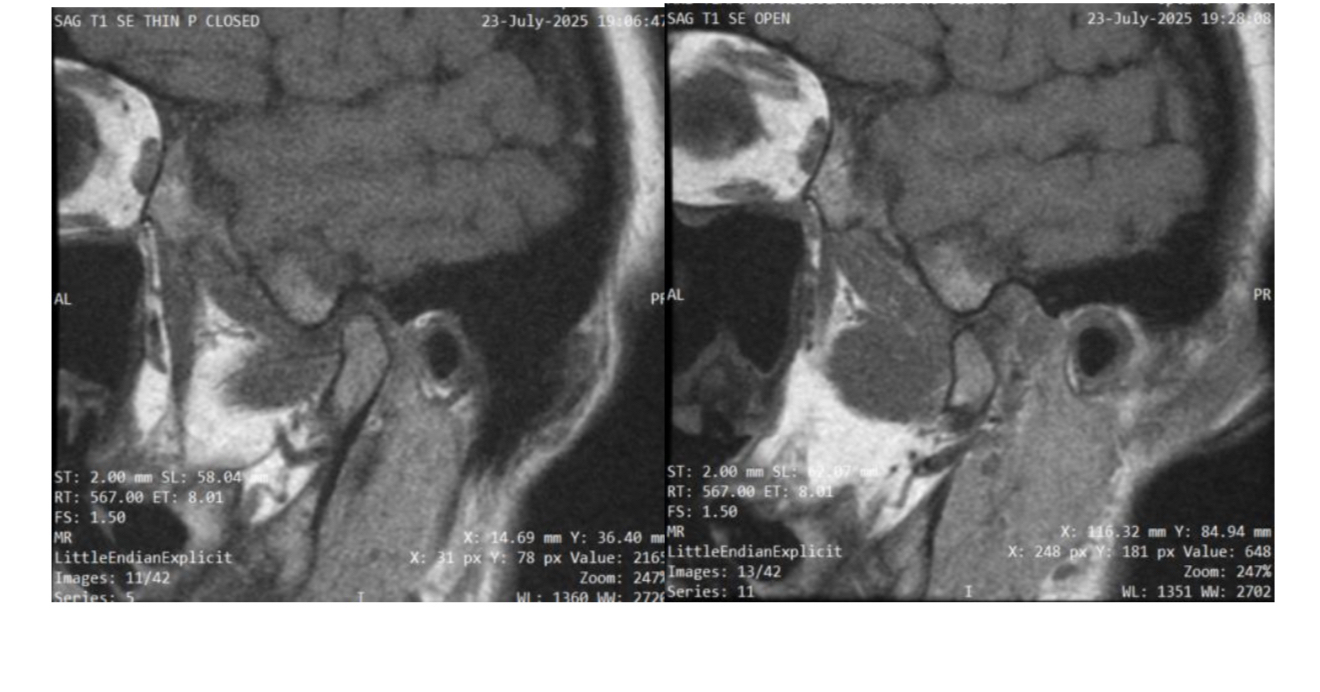

13

Q

What plane

A

Sagittal oblique TMJ (closed vs. open mouth)

How well did you know this?